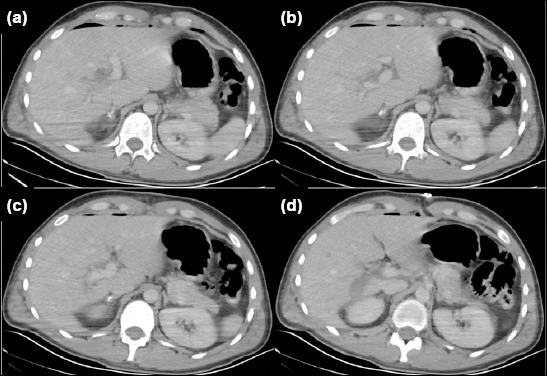

This report describes the successful treatment (without hepatectomy) of a patient who underwent laparotomy and bullet removal for a gunshot injury to the liver at another institution. The patient was later referred for hemobilia and was found to have an un-recognized tangential injury to the right portal vein branch, resulting in portal vein thrombosis, diagnosed on the twelfth day after injury. The patient subsequently developed severe cholangitis. Hepatic arteriography did not identify the source of hemobilia. Fol-lowing thrombectomy of the main portal vein and its left branch, along with portal vein repair, bilateral external biliary drainage from the common hepatic duct was performed. Hemobilia ceased after portal revascularization. A low-volume biliary fistula developed in the early postoperative period but resolved within 17 days with gradual removal of abdominal drains. The patient experienced no further complications during six months of follow-up. Standard biochemical blood tests remained within normal limits, except for slightly elevated alkaline phosphatase (167 U/L: 40-129) and gamma-glutamyl transpeptidase (100 U/L: 8-61) levels. Follow-up contrast-enhanced computed tomography scans on postoperative day 10 and at six months confirmed patency of the main portal vein and its left branch. Additionally, right lobe atrophy and left lobe hypertrophy were observed. In conclusion, applying principles from elective hepatopancreatobiliary surgery to trauma care, and avoiding major hepatectomy in the setting of severe cholangitis, played a crucial role in achieving a successful outcome.